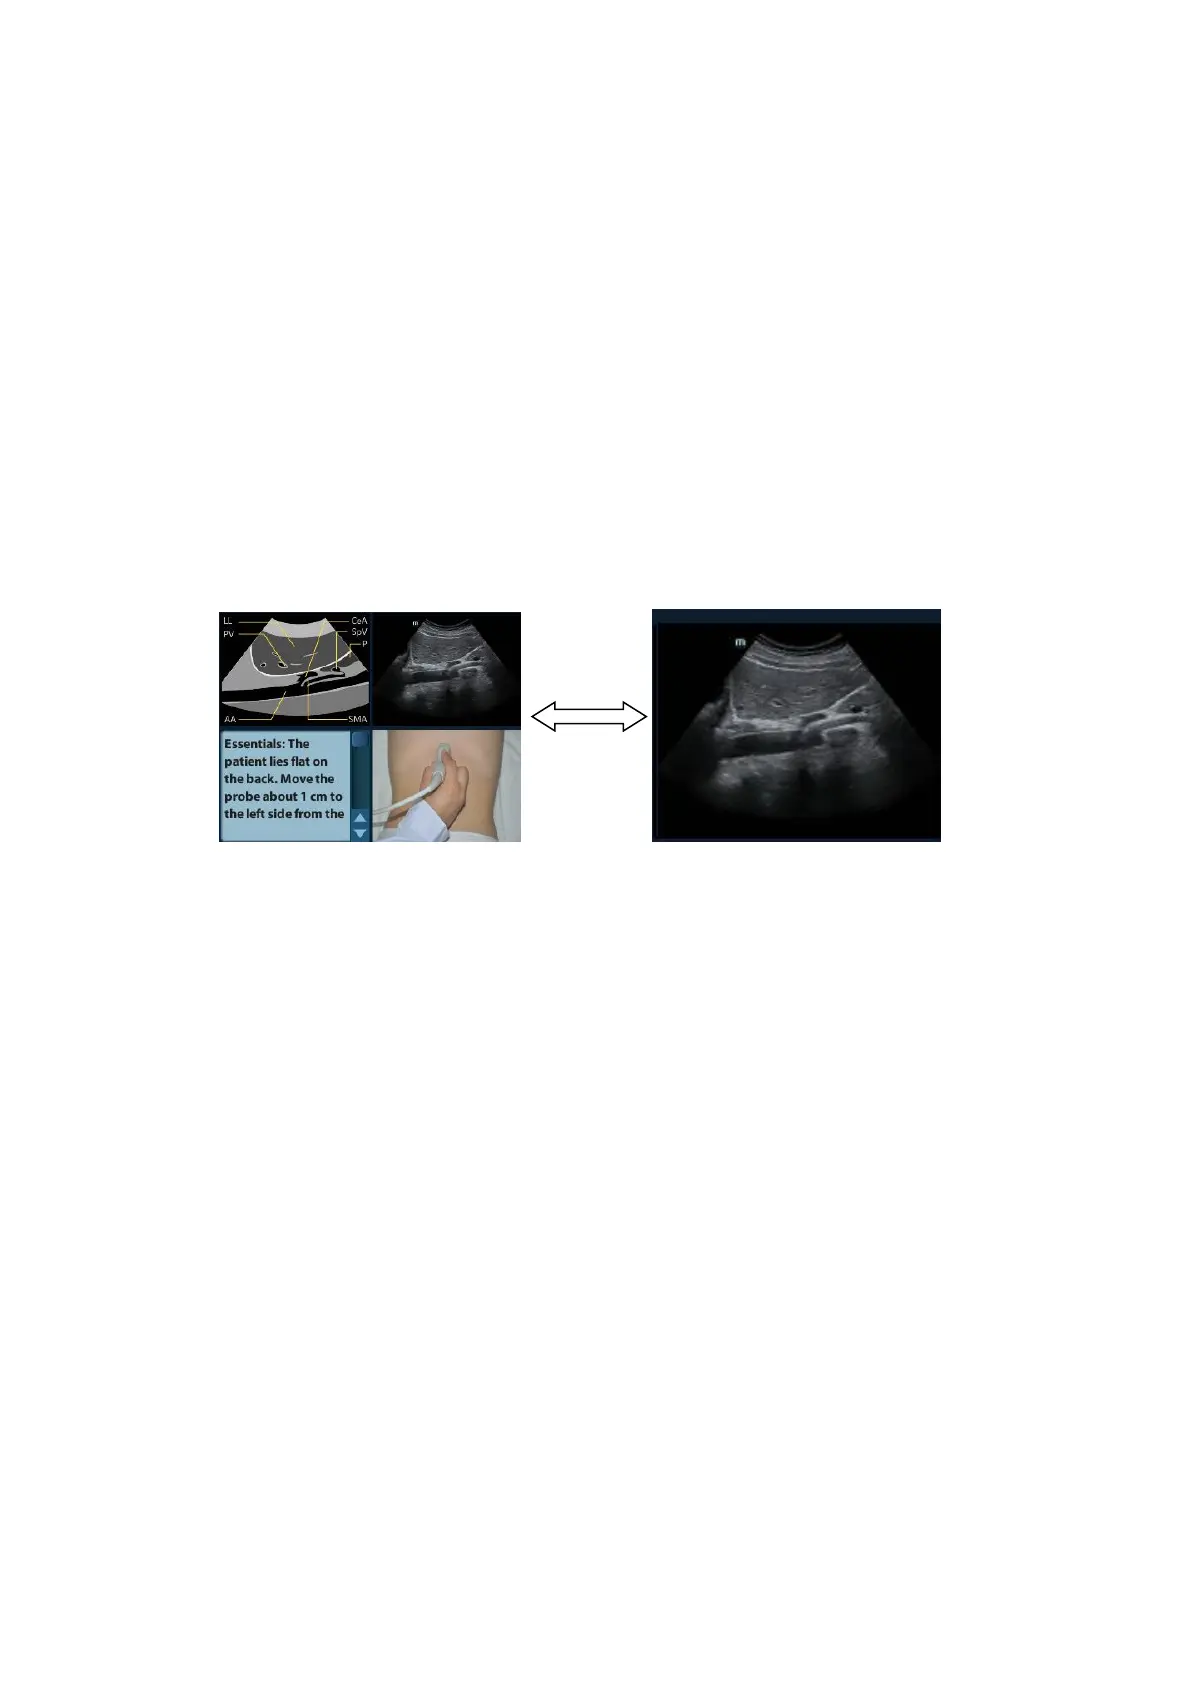

iScanHelper A-3

It is used to compare with images scanned by the operator.

Anatomic graphic

Related anatomical tissue information are provided here.

Scanning picture

Ordinary scanning tips can be observed here, including posture, probe mark, probe

swing/sweep techniques.

Scanning tips

You can read tissue related anatomical information and adjacent tissue information here.

A.4.3 Single/quad-window Display

You can zoom in the anatomic graphic, ultrasonic image as well as scanning picture to view

those information more conveniently.

Press <Cursor> to obtain the cursor. Move the cursor on the anatomic graphic, the ultrasonic

image or scanning tips. Double-click <Set> to go to the single window of each of them.

Double-click single window again to return to quad-window display.